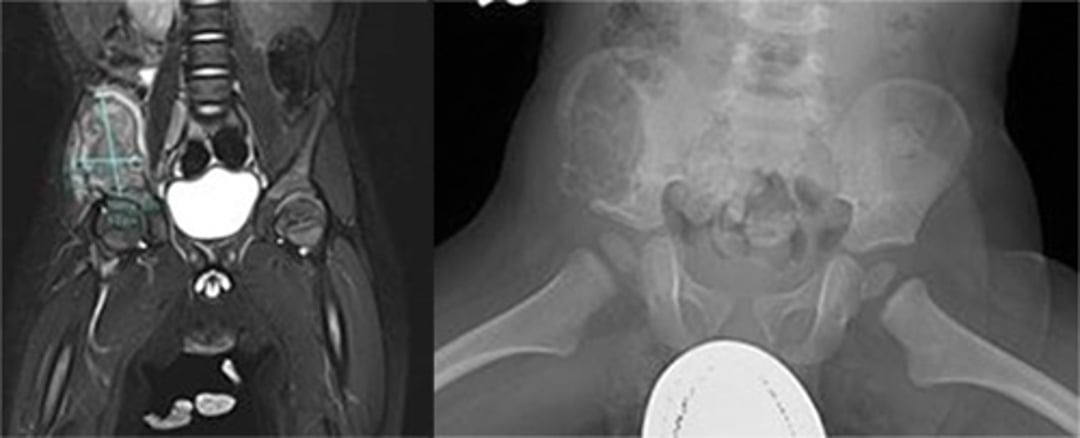

脳MRI(下垂体を評価するため)

脊椎MRI

腹部のCTまたはMRI(診察で肝脾腫が明らかになったか肝機能検査で異常を認めた場合)